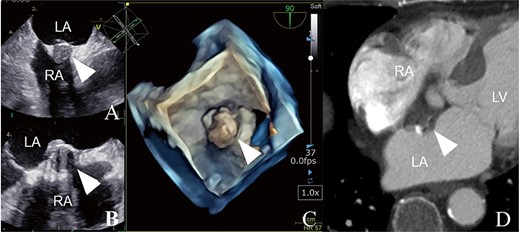

Preoperative examination findings (A–C): trans-esophageal echocardiography findings. (D) Enhanced computed tomography findings. Each image shows an IAS tumor with a solid mass and calcification suggesting a thrombotic IAS tumor (arrowheads). LA, left atrium; RA, right atrium; LV, left ventricle.

Intra- and postoperative histological findings. (A) Trans-right atrial view. The tumor is attached to the IAS wall. (B) The hard capsule with calcification. (C) Pathological findings. Concentric arrangement of cells around vascular cells, which is typical of myxomas.

Surgical tumor resection was performed under standard cardiac arrest via median sternotomy. The tumor was located at the fossa ovalis and was black-brown (Fig. 3A). The boundary between the tumor and healthy cardiac tissue was clear because the tumor was surrounded by solid connective tissue, with severe calcification (Fig. 3B). After tumor resection, an atrial septal defect was closed with a polytetrafluoroethylene patch (φ25 mm). The postoperative course was uneventful. Postoperative transthoracic echocardiography showed no residual tumors or shunt. Pathological examination revealed that the tumor was a myxoma (Fig. 3C).

Transesophageal echocardiography has high diagnostic specificity and sensitivity for cardiac tumor [2]; the differentiation is difficult due to their similar presentations on imaging. Furthermore, a thrombus may have a stalk [6]. We suspected the tumor to be a thrombus rather than a myxoma or another malignant tumor because it was solid and surrounded by calcification. Postoperative histological examination, however, concluded that it was a myxoma, indicated by the presence of an extracellular matrix of abundant myxoma cells clustered in rudimentary vascular formations (Fig. 3C).